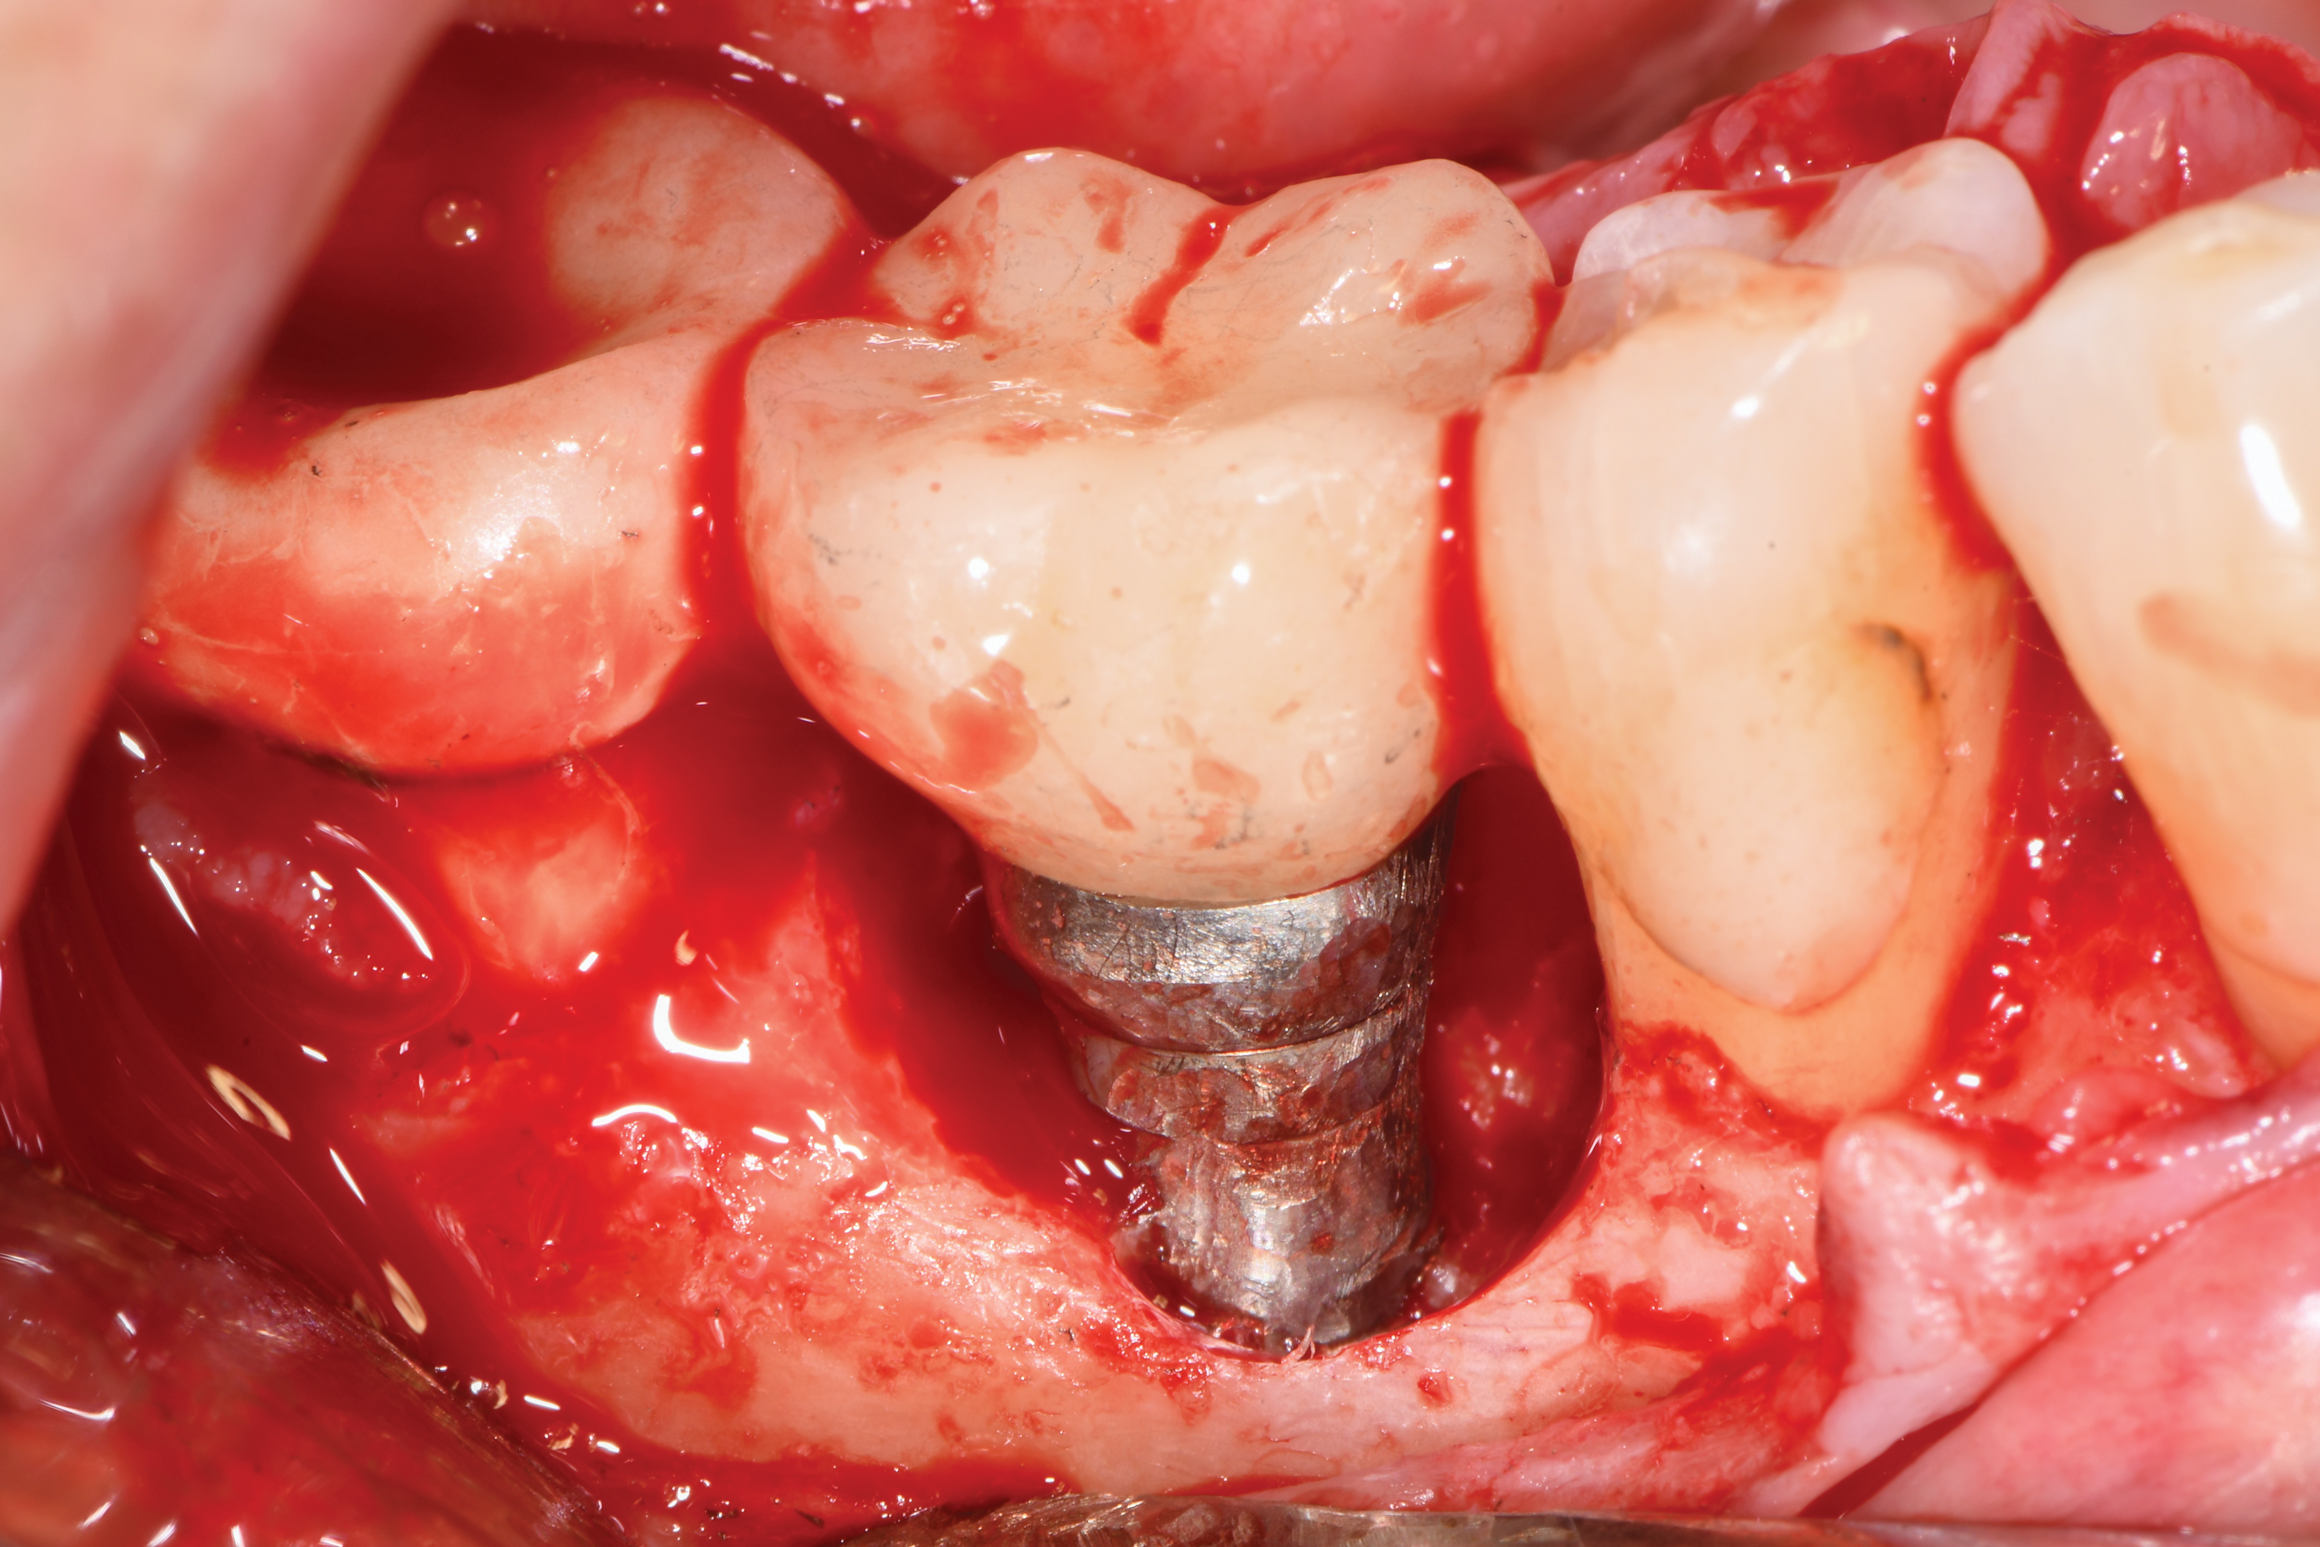

Fig 13. Implantoplasty was completed. Some bleeding at the distal obscured one thread that was impossible to plasty. The surface was subsequently wiped with citric acid prior to grafting.

Figure 13

After local anesthesia was administered, full-thickness flaps were elevated from the buccal and lingual aspects of tooth No. 27 to the distobuccal and lingual aspects of tooth No. 31. Removal of granulomatous tissue from the implant site allowed visualization of a combination lesion with two walls at the distal and two to three walls at the mesial with a circumferential configuration on the lingual (Figure 12). The surface was initially treated with a 50% solution of citric acid for 30 seconds, which was burnished on with cotton pellets followed by thorough rinsing with sterile saline. This was followed by implantoplasty using 12-fluted followed by 30-fluted surgical-length finishing burs that provided access to the base of the defect. Because the crown was cemented, which obviated access, a matte-like surface could not be achieved; thus, the goal was to reduce the threads and remove the outer affected surface to expose fresh titanium (Figure 13). At this stage, the implant was wiped again with citric acid and rinsed with sterile saline.